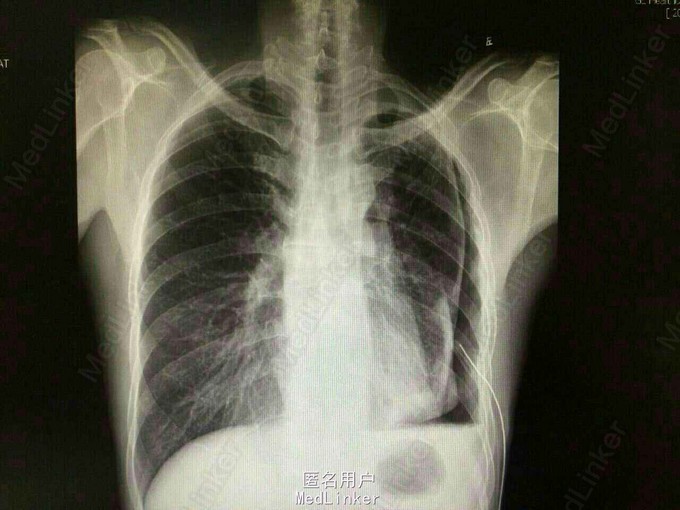

主诉:“左胸痛4月,加重伴气促1月”。 现病史:4月前出现左侧胸痛,咳嗽及吸气加重,1月前出现气促,活动后明显。于外院就诊,胸片提示:左侧大量胸腔积液,胸液CEA>1500ng/l,血CEA 33.67ng/L,CT示左侧液气胸,左上肺肿物,左胸膜增厚。予抗感染、胸腔闭式引流,气促好转。1周前晨起时出现咳血,为痰中带鲜血,约10ml/日。就诊于外院,诊断为“左下肺癌”,予以止血治疗(具体不详)后症状渐止。现来我院就诊,无肺外表现,无咳嗽、胸痛等其他特殊症状。

体查:浅表淋巴结无肿大,胸廓形态无畸形。左侧呼吸音弱。 胸片(2015-4-16):左侧液气胸,肺压缩约50%;左上肺纤维增殖灶;左上胸膜增厚粘连。 支气管镜检查:左右主支气管及各叶段支气管管腔通畅,粘膜光滑,分泌物不多,未见新生物及出血。 予以左胸腔闭式引流术。复查胸片(2015-4-22):左侧液气胸,与2015-4-16片对比,肺组织有所复张,肺压缩约22%。